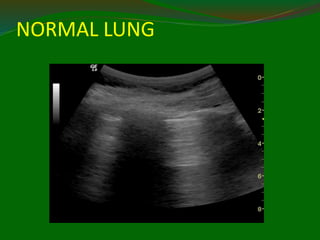

Lungs –normal static findings

Normal lung considered “invisible” to

ultrasonographer Artefact scan be used to infer

normality or abnormality

A lines horizontal reverberation artifacts from

pleural line the only finding in 2/3 of normal lung

US

B lines vertical narrow bands from pleural line to

edge of screen obliterate the A line

Multiple B lines = Ultrasound Lung Rockets =

Abnormal lung has characteristics that are

clinically useful

NORMAL LUNG

A lines = default normal

 Horizontal echo

reflection at exact

multiples of

intervals from

surface to bright

reflector.

 Dry lung

 Decay with depth

 Obliterated by B